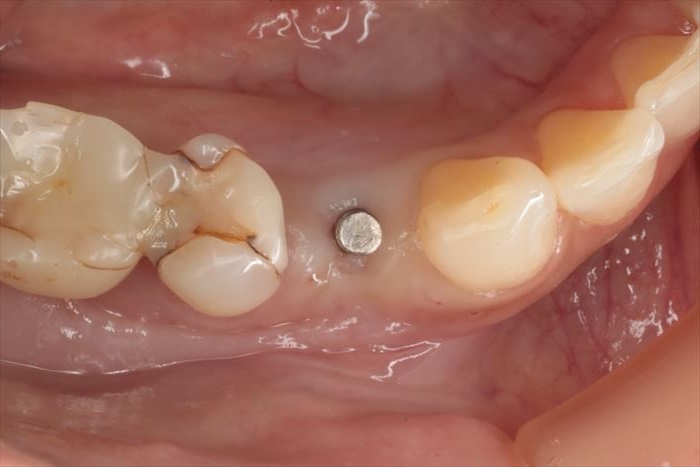

インプラント埋入から6週後の状態です。(2025.10.24)

CO2レーザーで歯肉を蒸散してインプラントのマージンを露出させます。